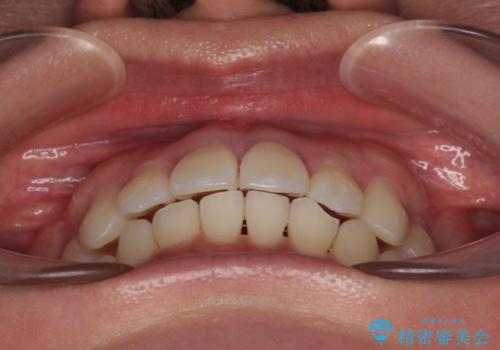

デコボコと正中のずれを改善した矯正治療

- 「歯並び全体のデコボコが気になる」「上下の歯の正中(中心)がずれているのが気になる」

このようなお悩みを主訴にご来院された患者様の矯正治療症例をご紹介します。

初診時、上下顎ともに歯列の不正が認められ、特に左下の小臼歯が大きく歯列から外れている状態でした。その影響により、下顎の正中が左側へシフトしており、見た目だけでなく噛み合わせにも影響が出ていました。